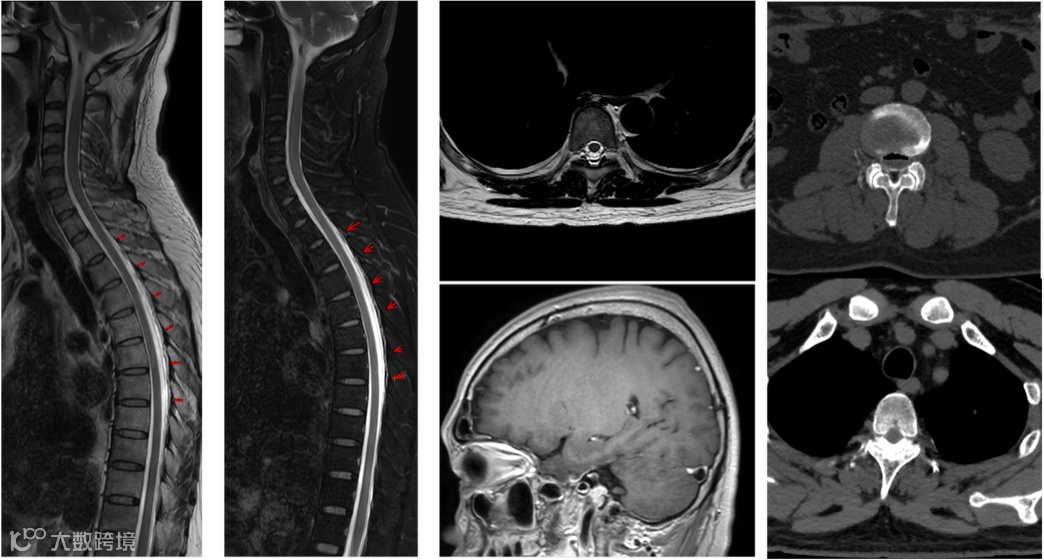

2025-10-14 头颅MR增强+MRV+颈椎MR平扫 影像号:3515491

2025-10-16 颈椎+腰椎MR平扫 影像号:3515491

2025-10-20 颈胸腰椎CT增强 影像号:2569557HY

影像学表现